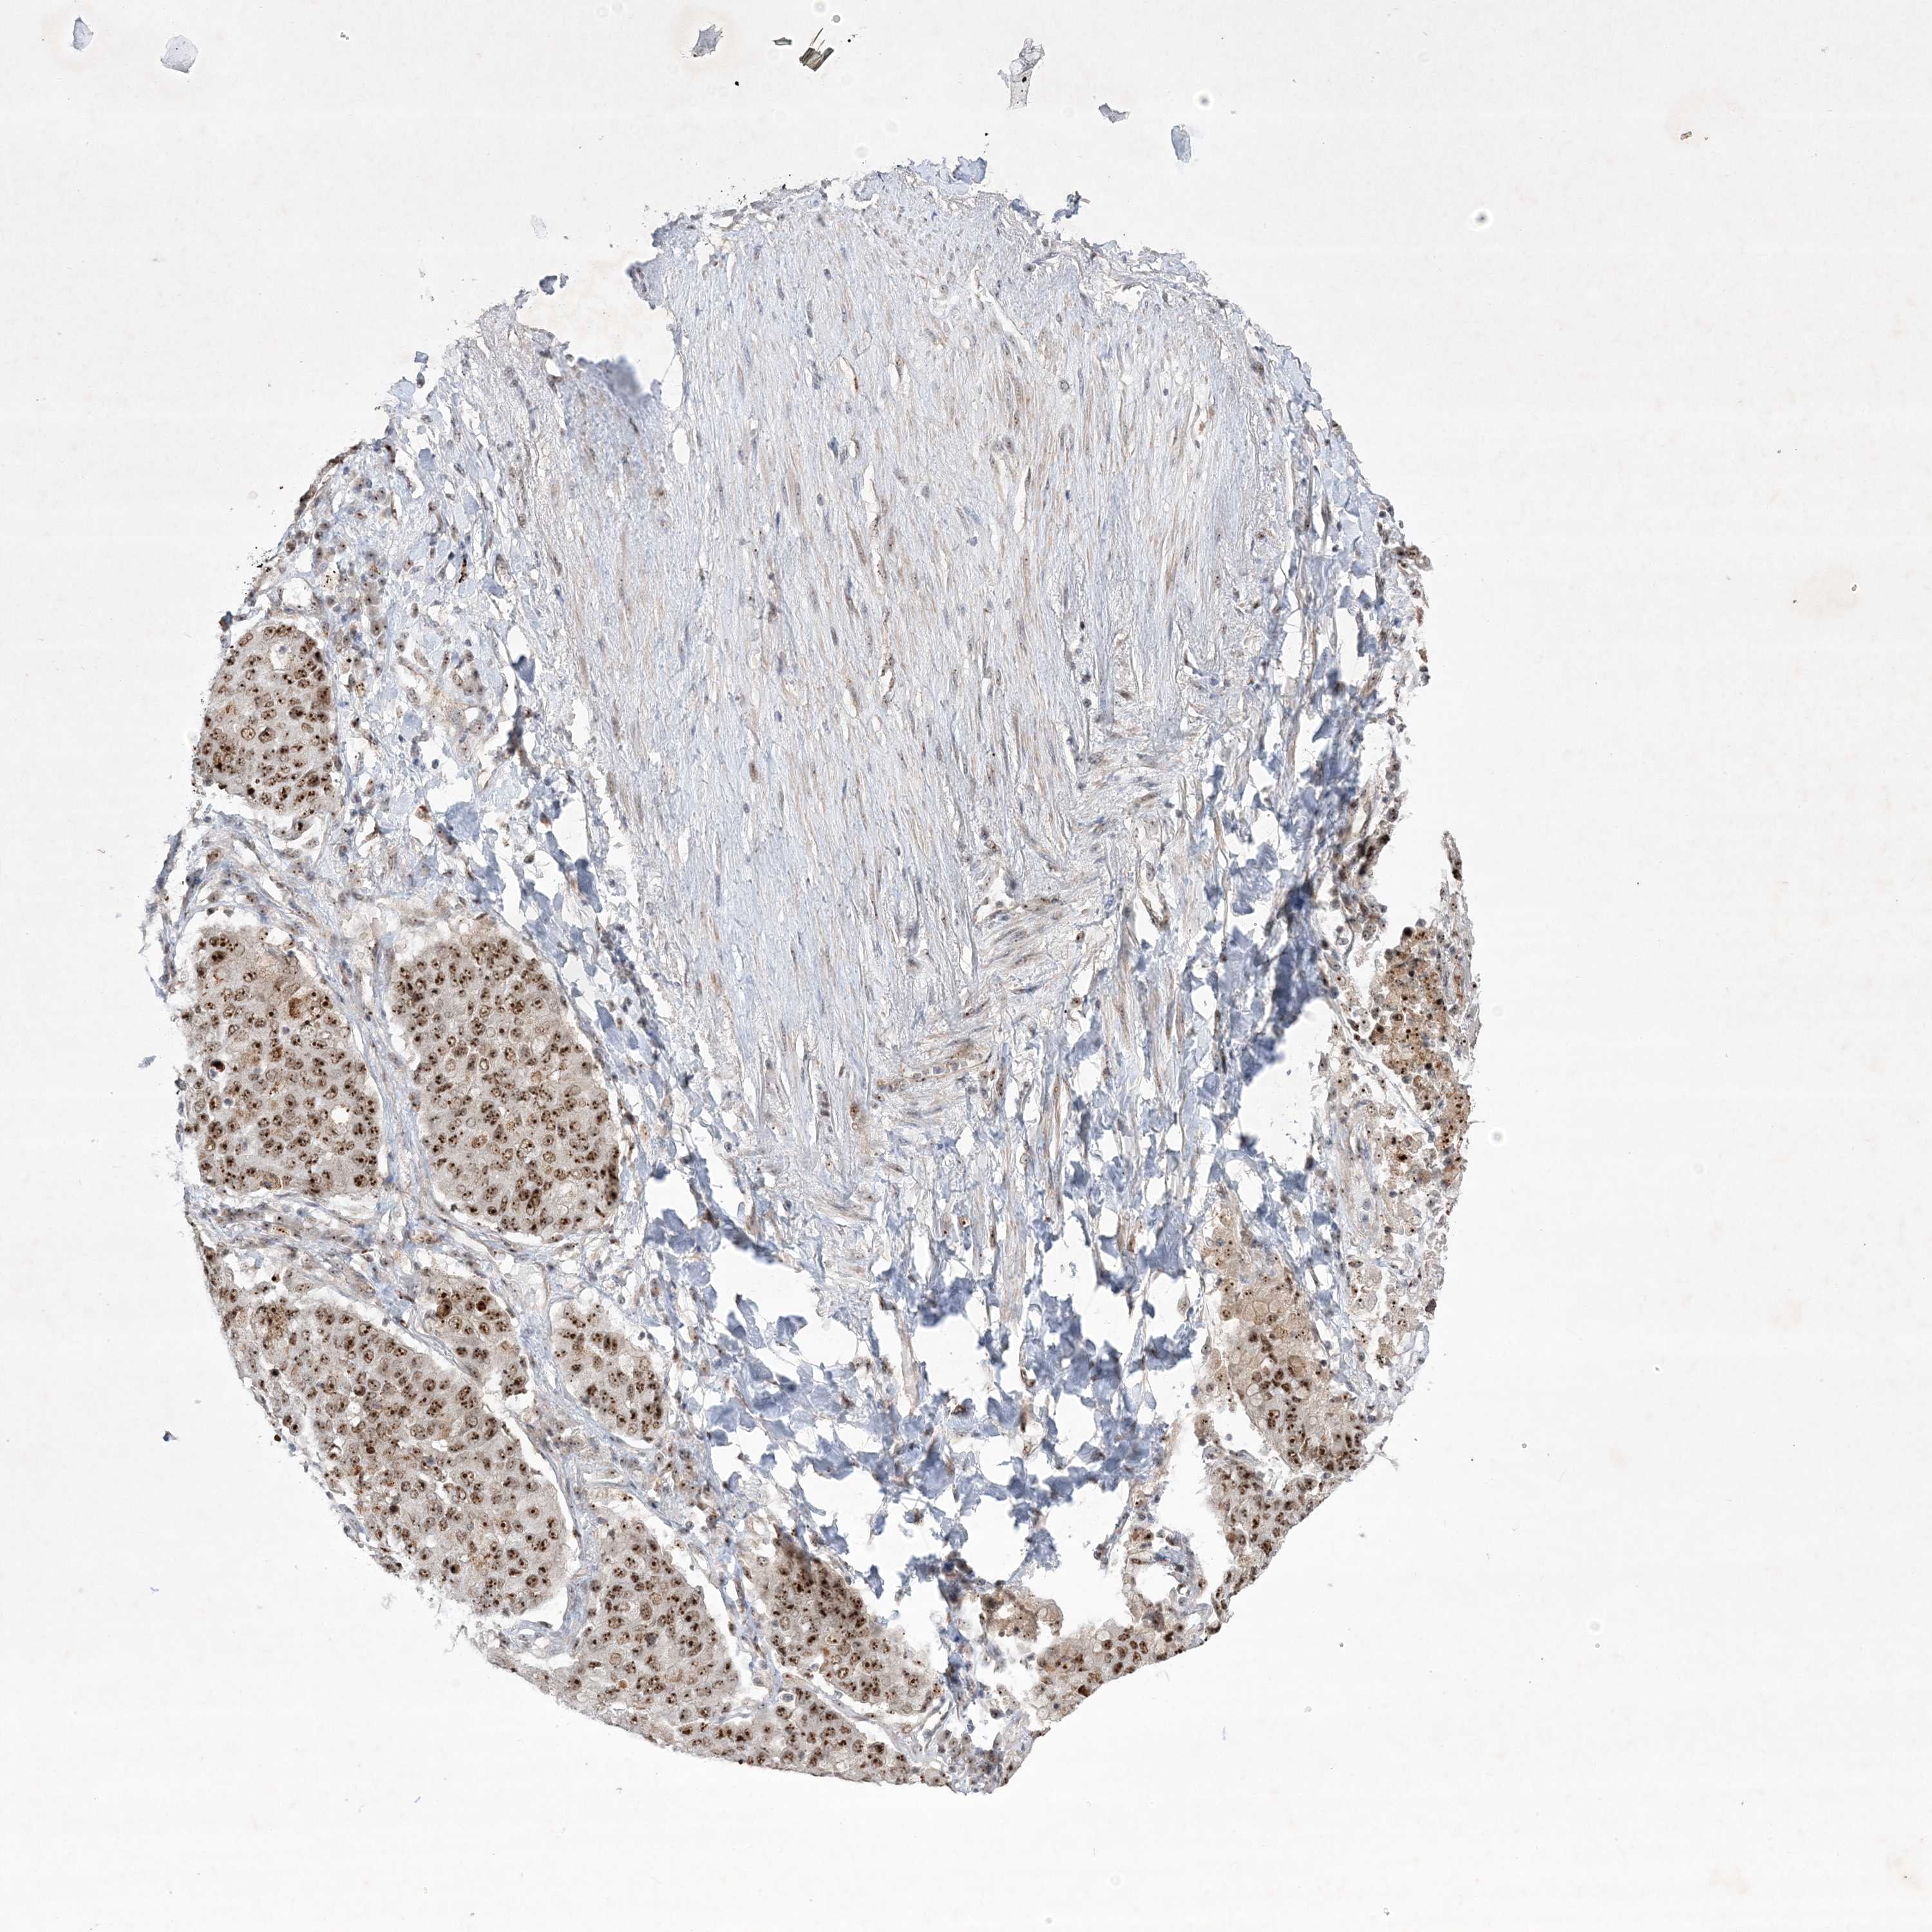

CANCER LUNG CANCER Show tissue menu

LUAD TCGA LUAD VALIDATION LUSC TCGA LUSC VALIDATION PROTEIN LUAD CPTAC PROTEIN LUSC CPTAC PROTEIN EXPRESSION

ANTIBODIES

AND

VALIDATION